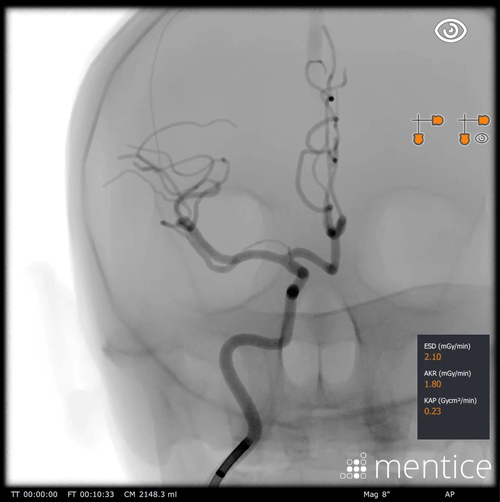

Acute Ischemic Stroke (AIS)

Hands-on training for image-guided interventional treatment of acute ischemic stroke

The AIS cases teach specific skills for treating neurovascular thrombectomy, focusing on the basic steps of aortic and supra-aortic access, direct aspiration, and mechanical thrombectomy using retrievers and a combined technique.

Assess the location of the occlusion, as well as the tortuosities of the access path, using angiograms